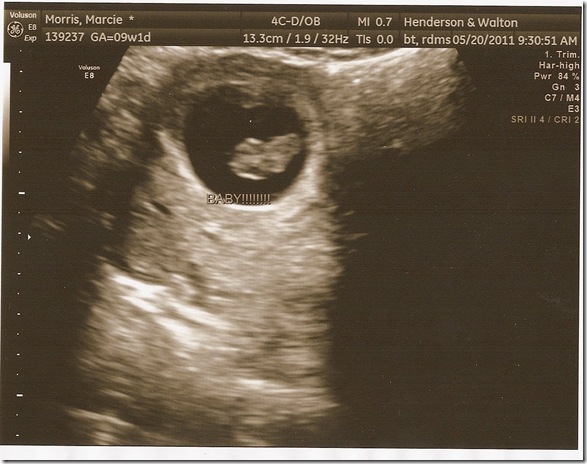

So our ultrasound was Friday, May 20th. I was so nervous. I knew that the miscarriage rate decreased significantly once you heard the heartbeat so I was trying to hold it together and not run too many “what if” scenarios through my head. Justin and I got called back and to my surprise they did the ultrasound from on top of my stomach, not the other way in which most first ultrasounds are done!! I was pumped about that part. I was praying so hard at that moment that she was searching on my stomach and looking at the screen. Finally the tech said “well it looks like you only have one baby in there”. Thank God for that! Then she turned the screen towards me and showed me the baby. Then she zoomed in super close and pointed to the heart that I could see was moving SO fast. She turned on the volume and I heard the most precious sound ever. I cried. Heart beat was 185 bpm. She said everything looked great so far. I’m so thankful for that! Here’s Won Ton’s first pictures:

They say 9w1d which means 9 weeks 1 day, which is what they thought I was at the time, but we got downgraded to only 8 weeks 3 days after she measured the baby. I can’t wait to hear the heart again. I only got to hear it for about 3 seconds and I really want to hear it for longer next time.